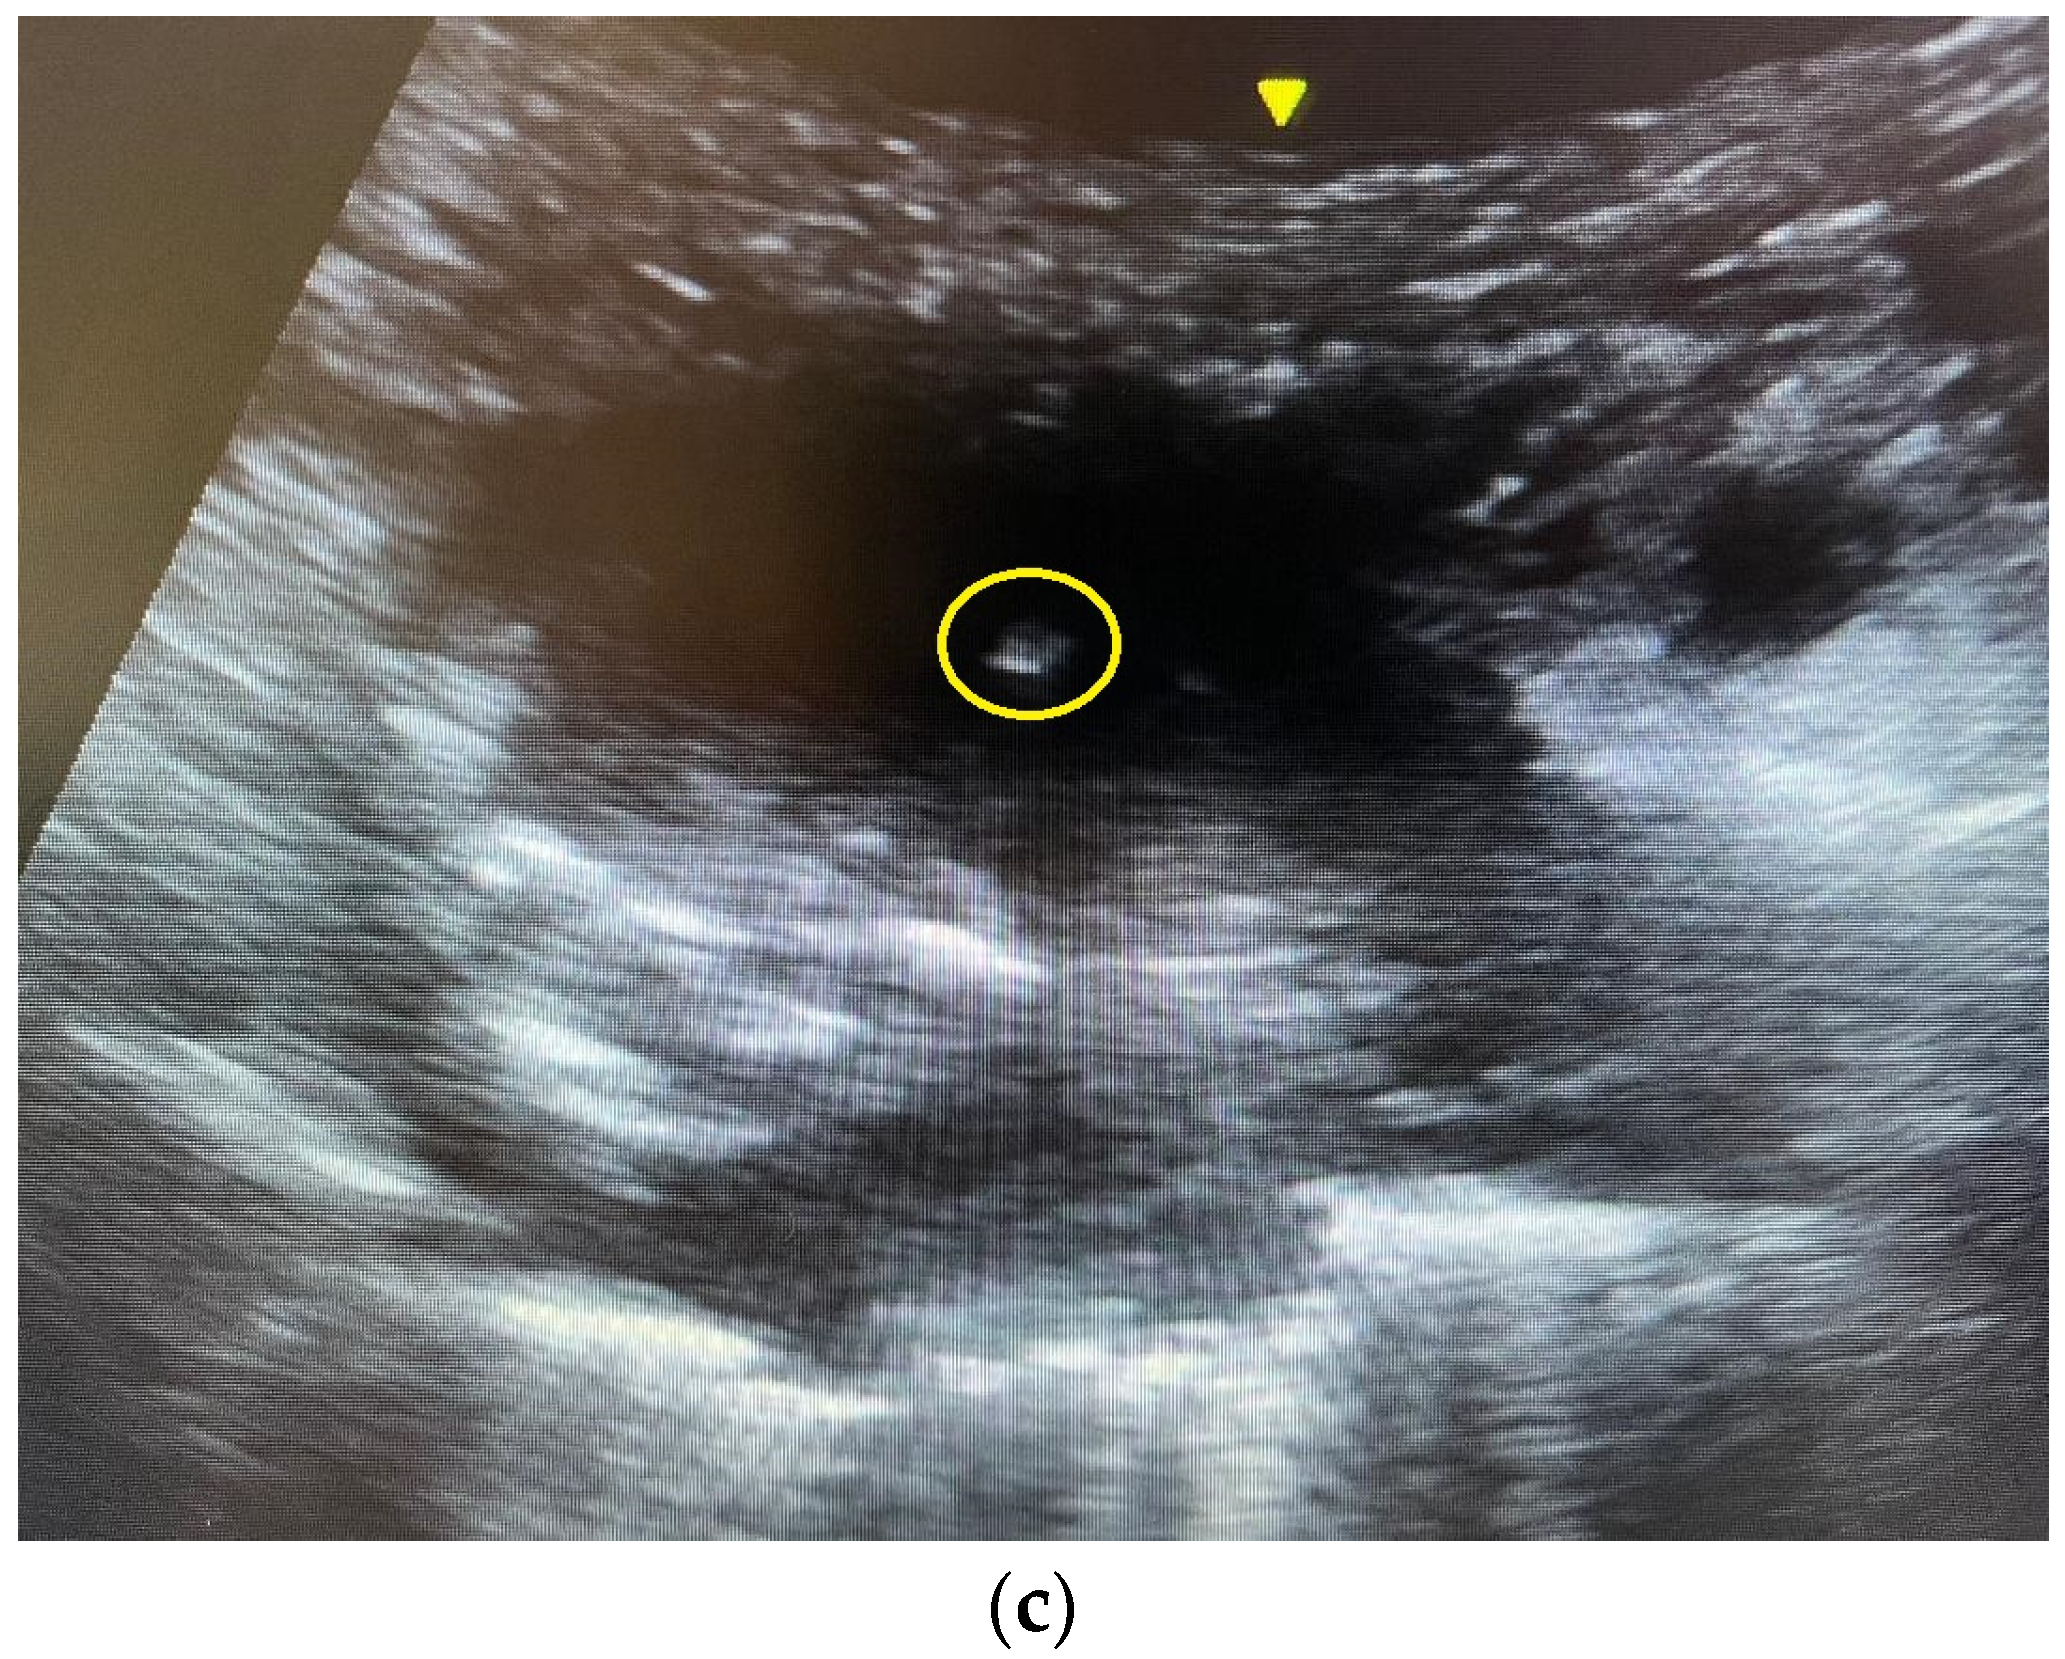

Patients were instructed to sit upright, lie supine or lie lateral. The ultrasound machine Venue 40® or Venue 50® (General Electric, Boston, MA, USA) with curvilinear probe was used to locate the lesion. Color Doppler was employed to check for vessels running through the lesion. The operators would avoid puncturing the vessels during FNA. Under real-time ultrasound guidance and aseptic technique, 5 mL 2% lignocaine was injected percutaneously for local anesthesia. A 22-gauge (22 G) Spinocan® spinal needle (B. Braun, Melsungen, Germany) was inserted, and the needle tip’s position within the target lung lesion was confirmed using a real-time ultrasound exam in the short axis or long axis (Figure 1). The needle stylet was then removed, and a 20 mL syringe was attached to the needle. Four to five in and out motions were made with the needle. At the same time, suction was applied via the 20 mL syringe. Cytological material obtained was injected into a formalin bottle. At least two punctures were made.

Figure 1. (a) A computed tomography image showing a right upper lobe Pancoast tumor. The tumor closely abutted the chest wall, allowing ultrasound-guided percutaneous biopsy. The pathology was squamous cell carcinoma. (b) An ultrasound image of the Pancoast tumor. The tumor had soft tissue density with heterogeneous echogenicity. (c) The yellow circle indicated the position of the needle tip inside the tumor. Several in and out motions were made with the needle, and the needle tip’s position was traced inside the tumor under real-time ultrasound guidance.